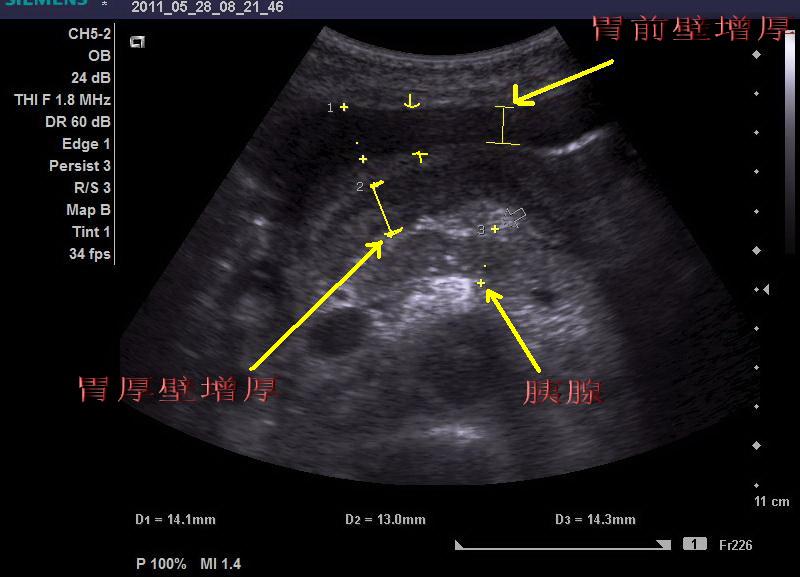

皮革胃

图片尺寸800x577